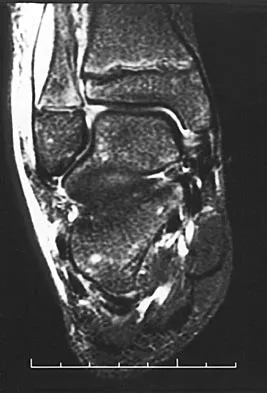

Question 48High Yield

An 11-year-old boy has had a fever and pain and swelling over the lateral aspect of his right ankle for the past 3 days. Examination reveals warmth, swelling, and tenderness over the lateral malleolus, and he has a temperature of 103.2 degrees F (39.5 degrees C). Laboratory studies show a WBC count of 13,200/mm3 with 61% neutrophils, an erythocyte sedimentation rate of 112 mm/h, and a C-reactive protein of 15.7. Radiographs and a T2-weighted MRI scan are shown in Figures 13a through 13c. Aspiration yields 1 mL of purulent fluid. Management should now consist of

Explanation

The initial signs and symptoms of acute hematogenous osteomyelitis vary widely but usually include fever, bone pain, and impaired use of the involved extremity. In lower extremity infections, the child may limp or refuse to walk. Examination often reveals bone tenderness. In more advanced cases, erythema, warmth, and swelling may be present. The WBC and neutrophil counts are not always elevated, but the erythocyte sedimentation rate will be abnormal in more than 90% of patients. When the infection is diagnosed early, before a subperiosteal abscess has formed, antibiotics alone may be adequate to treat the infection. This patient has a more advanced infection, however, with the MRI scan revealing a subperiosteal abscess that was confirmed by aspiration. When an abscess is present, surgical drainage is generally indicated to remove devitalized tissue and to enhance the efficacy of the antibiotics. Further studies, such as bone or indium scans, are not necessary and will delay definitive treatment. Scott RJ, Christofersen MR, Robertson WW Jr, et al: Acute osteomyelitis in children: A review of 116 cases. J Pediatr Orthop 1990;10:649-652.